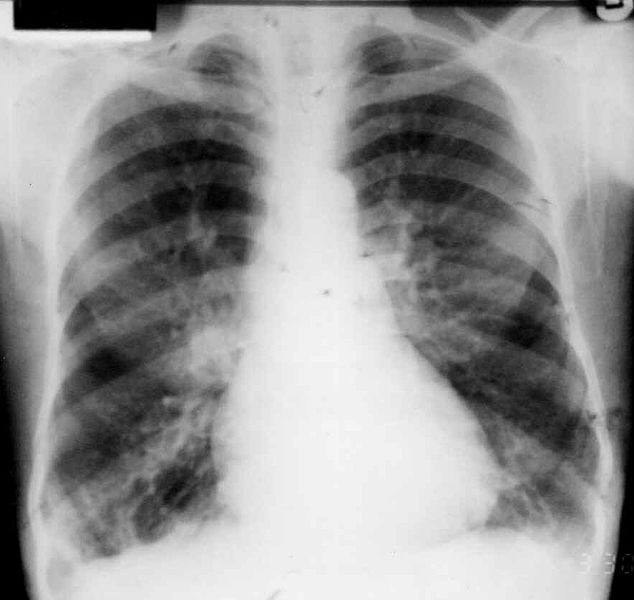

기관지 확장증 가슴 방사선 검사 (출처 : 위키 미디어)

기관지확장증을 확인하기 위한 검사는 여러 가지가 있습니다. 필수적인 검사는 가슴 방사선 검사(엑스레이)입니다. 가슴 방사선 검사는 비특이적입니다. 무슨 말이냐 하면, 가슴 방사선 검사는 기관지확장증을 확인하고 진단하는데 부정확하고 다른 질병과 헷갈릴 수 있다는 것입니다.

경한 기관지확장증이면 심지어 가슴 방사선 검사는 거의 정상 소견으로 보이기도 합니다. 심한 기관지확장증일 때 가슴 방사선 검사를 해보면 기관지확장증을 시사하는 기관지 내부에 낭성 병변이 보이기도 합니다. 그러나 이런 모양은 수포성 폐기종이나 간질성 폐렴에서도 마찬가지로 비슷하게 보일 수 있어 기관지확장증과 종종 헷갈리기도 합니다.

이렇게 부정확한 검사지만 필수적인 이유는 검사하기 간단하면서도 바로 과거의 가슴 방사선 검사와 비교를 할 수 있기 때문입니다. 예전에 찍은 가슴 방사선 검사와 대조해 보면서 변화 추이를 보는 것이 가장 중요하며 변화 양상으로 많은 정보를 알 수 있습니다,